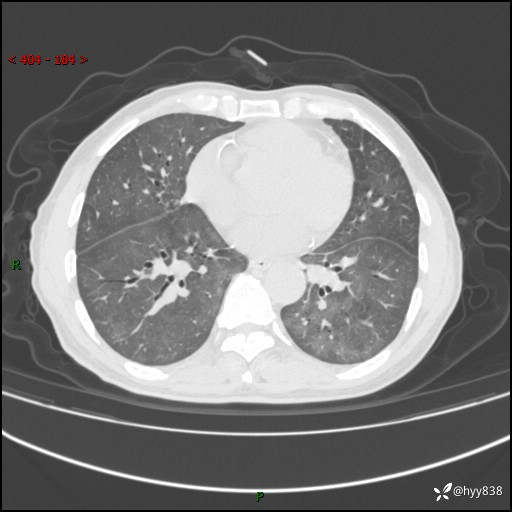

肺结节入院,CT却发现肺部弥漫性病变,what happened---(有结果)

主诉:检查发现左上肺结节4天

简要病史:患者于2024-01-15当地市人民医院胸部CT提示:左肺上叶(69)结节,最大截面约1.0 x 1.2cm,肿瘤病变待排。现患者活动后呼吸困难,自述平地行走200m后胸闷气喘,不伴咳嗽咳痰、头晕、恶心、呕吐等不适,未行特殊处理。现患者为求进一步治疗,于我院就诊,门诊拟“左上肺结节”收入院。 自患病以来患者食欲差,精神、睡眠尚可,大小便正常,体重近1月来下降5kg左右,体力明显减轻。

辅助检查:CT

胸部CT平扫

不是讨论肺部结节